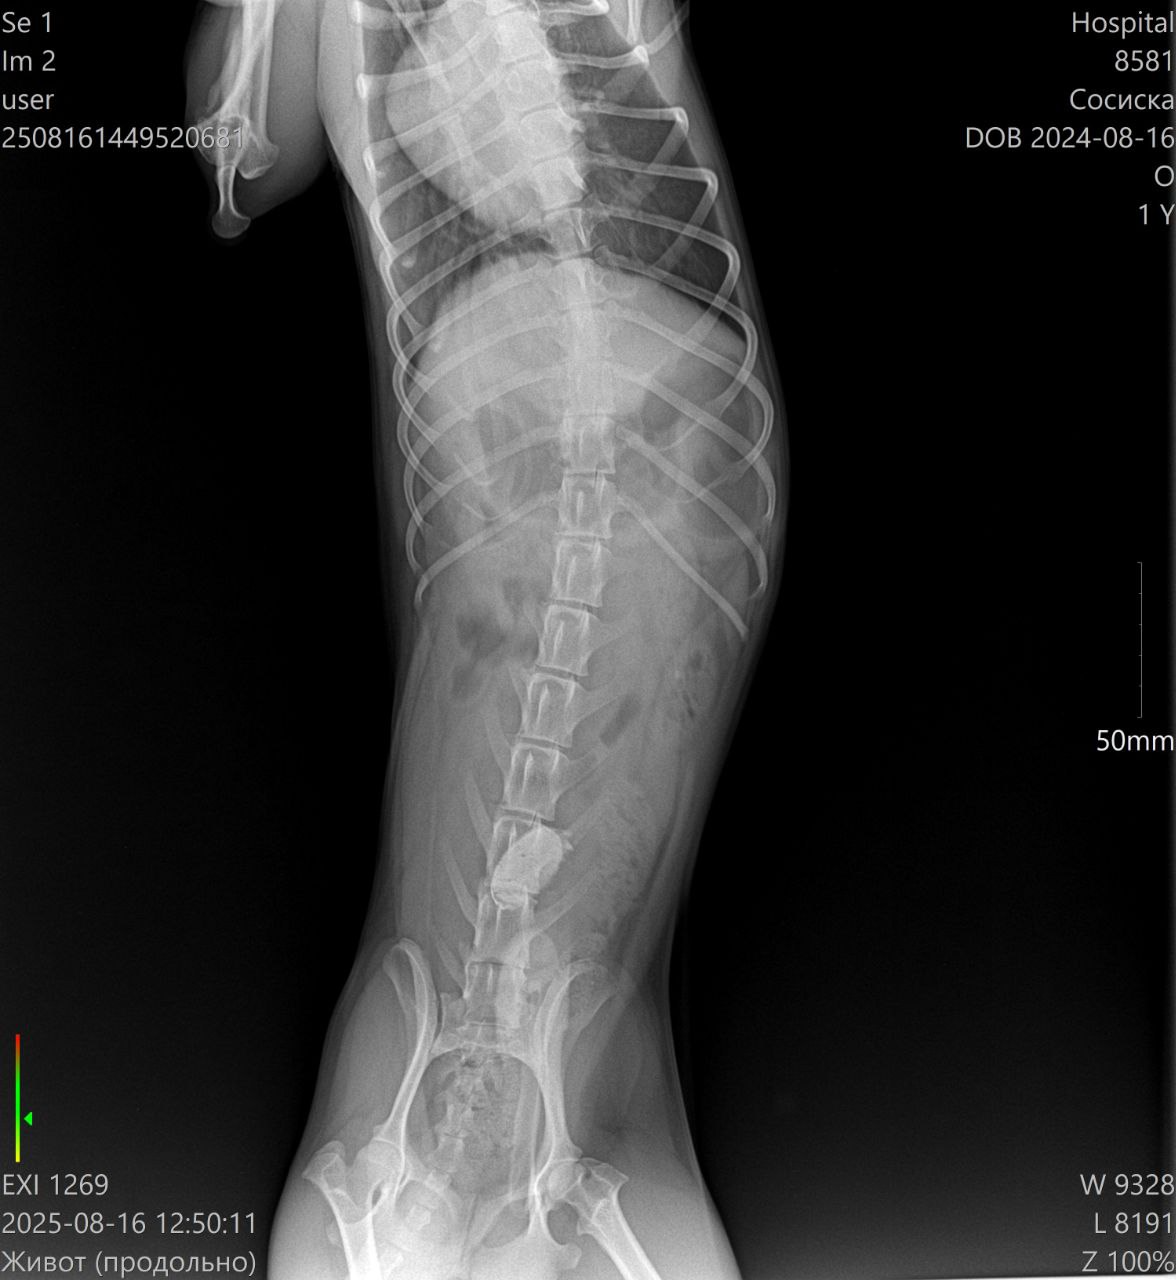

Ветеринарная клиника: измерение температуры, сделали УЗИ - в желудке обнаружена какая-то инородная штука, или показалось или... завтра на операцию

Клизмы и прочие смазки не уговорили отдать то ли крышку, то ли ещё что-то такое металлическое

Врачам пришлось резать сосиску и извлекать инородное тело